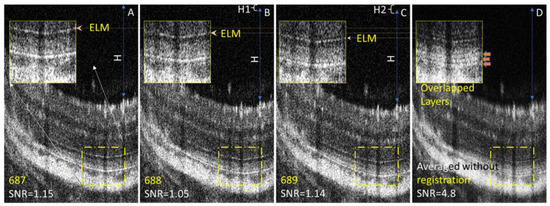

3.1. Registration: Classical, A.I., and Hybrid

Homography Transformation Approaches